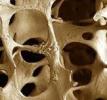

Osteoporosi, ancora oggi è difficile riconoscerlaNonostante alcuni sintomi siano inconfondibili, nella maggior parte dei casi l’osteoporosi risulta asintomatica. Ecco perché è importante sottoporsi a controlli preventivi a partire dai 30 anni Sono oltre 200 milioni le persone nel mondo affette da osteoporosi, ma nonostante ciò questa condizione molto spesso non viene riconosciuta o non si riesce a diagnosticarla a causa della sua asintomaticità. La maggior parte delle persone infatti, scopre di essere...